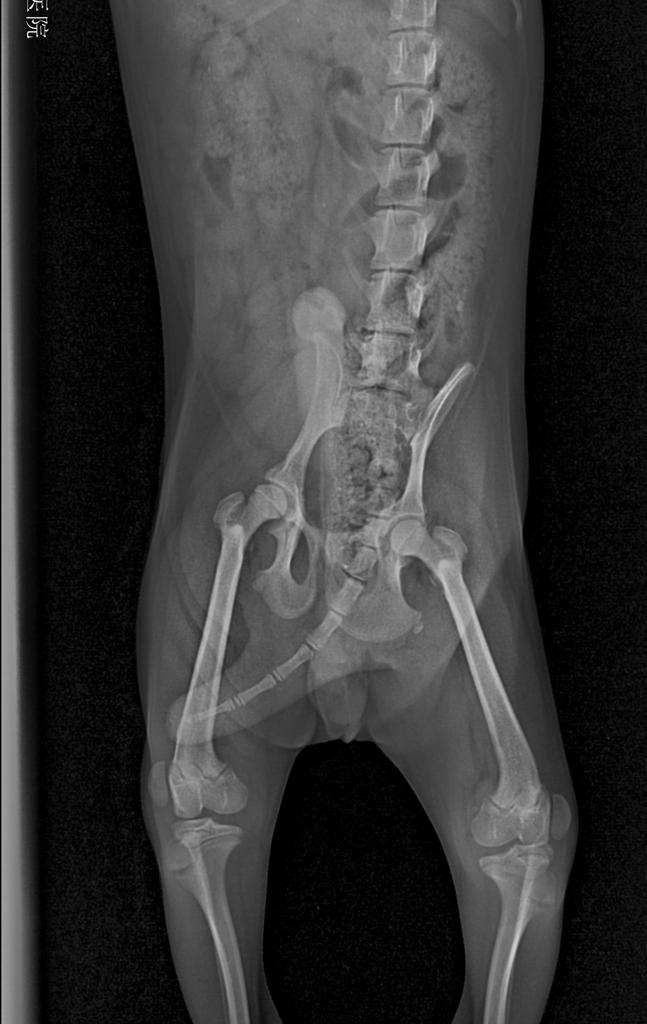

髌骨脱位如何确诊呢?

根据主人的症状描述,没有任何外伤和刺激狗狗突然后腿不敢着地,然后跑起来会自行恢复,配合宠物医生的髌骨部位触诊,以及照射x光后,即可确诊。